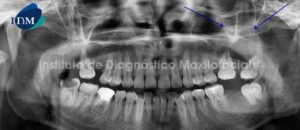

Paciente de sexo femenino y de 21 años de edad es referida al Instituto de Diagnóstico Maxilofacial para la evaluación de su estado dental y periodontal.